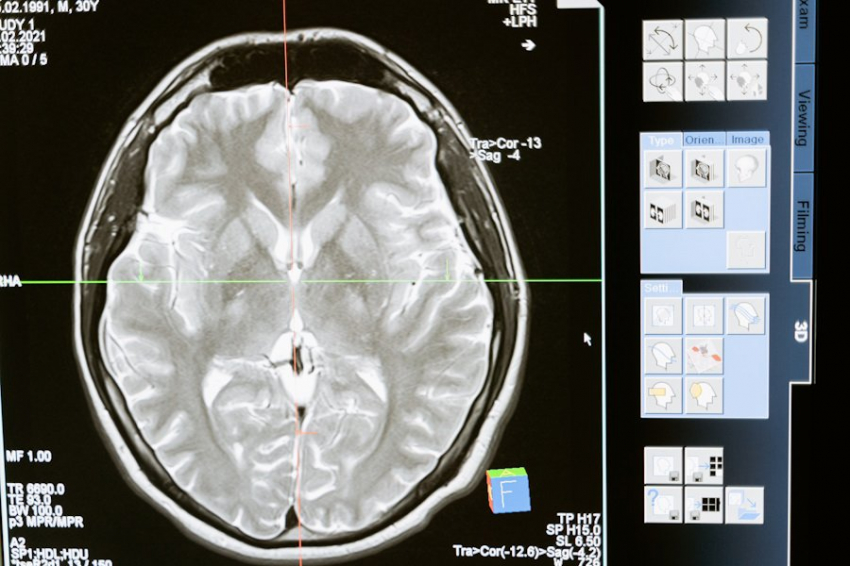

Фото из открытых источников

Рассеянный склероз — это воспалительное и нейродегенеративное заболевание центральной нервной системы, которое приводит к прогрессирующей неврологической инвалидности. До сих пор исследования в основном сосредотачивались на роли иммунной системы в развитии РС, однако вклад дисфункции клеток центральной нервной системы оставался неясным.